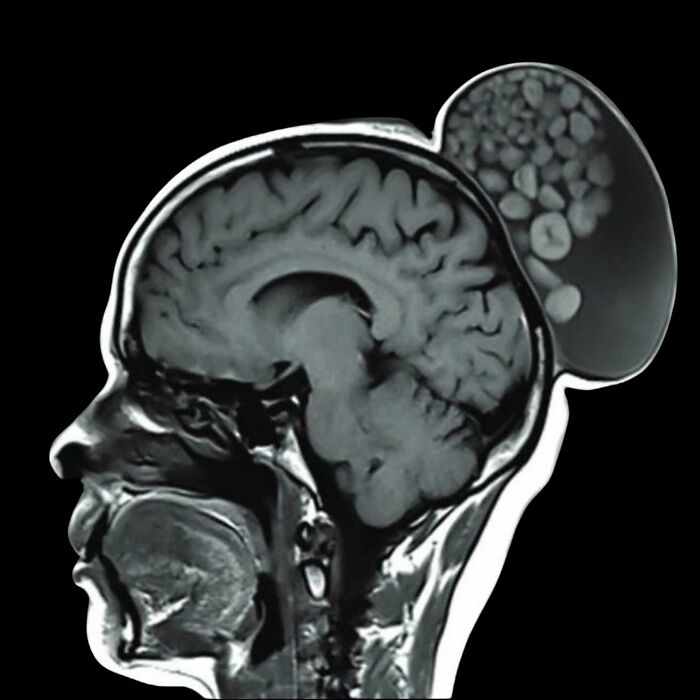

En una cirugía inusual, médicos de Bengaluru extirparon una protuberancia de la cabeza de una mujer que parecía un saco de canicas.

El término médico para estos glóbulos es quistes dermoides. Son esencialmente esferas de tejido que se forman a partir de células embrionarias y pueden contener cabello, dientes o nervios.

Estos glóbulos pueden aparecer en cualquier parte del cuerpo, incluyendo los ovarios y diversas zonas de la cabeza y el cuello.

Los quistes dermoides suelen ser inofensivos, pero no se curan por sí solos y requieren extirpación quirúrgica.